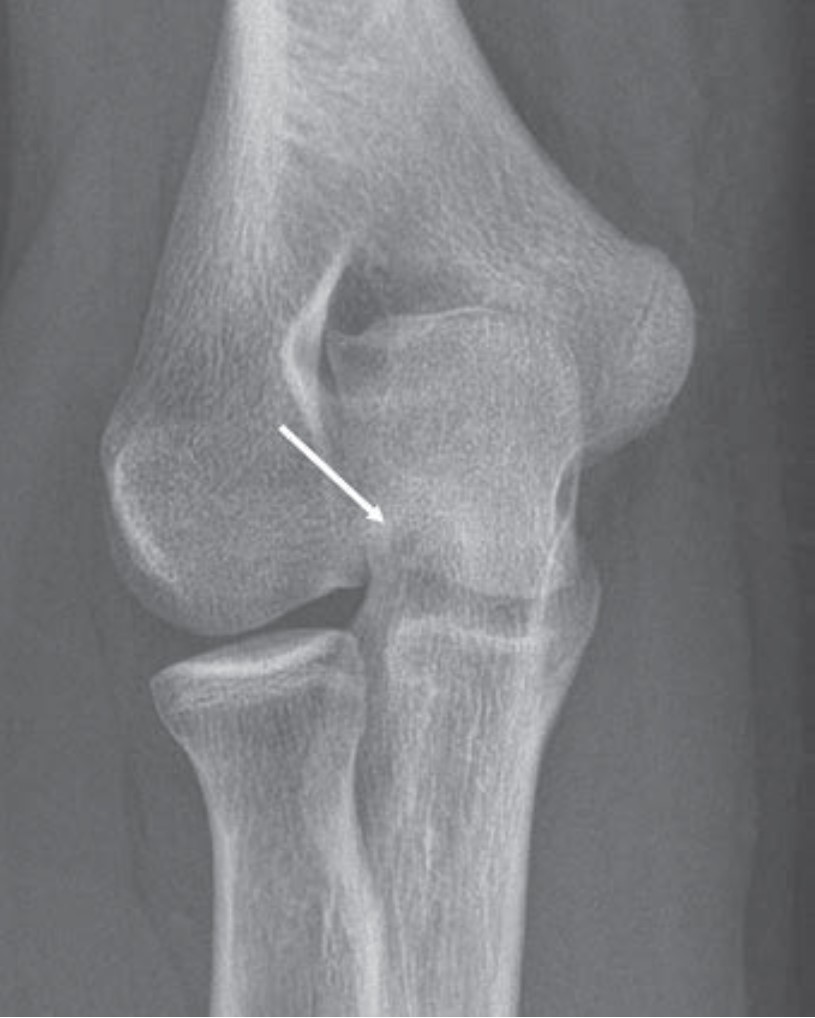

Lateral Trochlear Osteochondritis Dissecans of the Elbow: A Rare and Subtle Finding With Important Implications for Management

Given the overlapping ulnar anatomy and subtlety of its radiologic features, even experienced radiologists can miss lateral trochlear osteochondritis dissecans (OCD) of the elbow. As the first Don’t Miss This article in R3 notes, early identification of lateral trochlear OCD allows for appropriate activity modification, as well as timely intervention to mitigate lasting disability (Fig. 6).